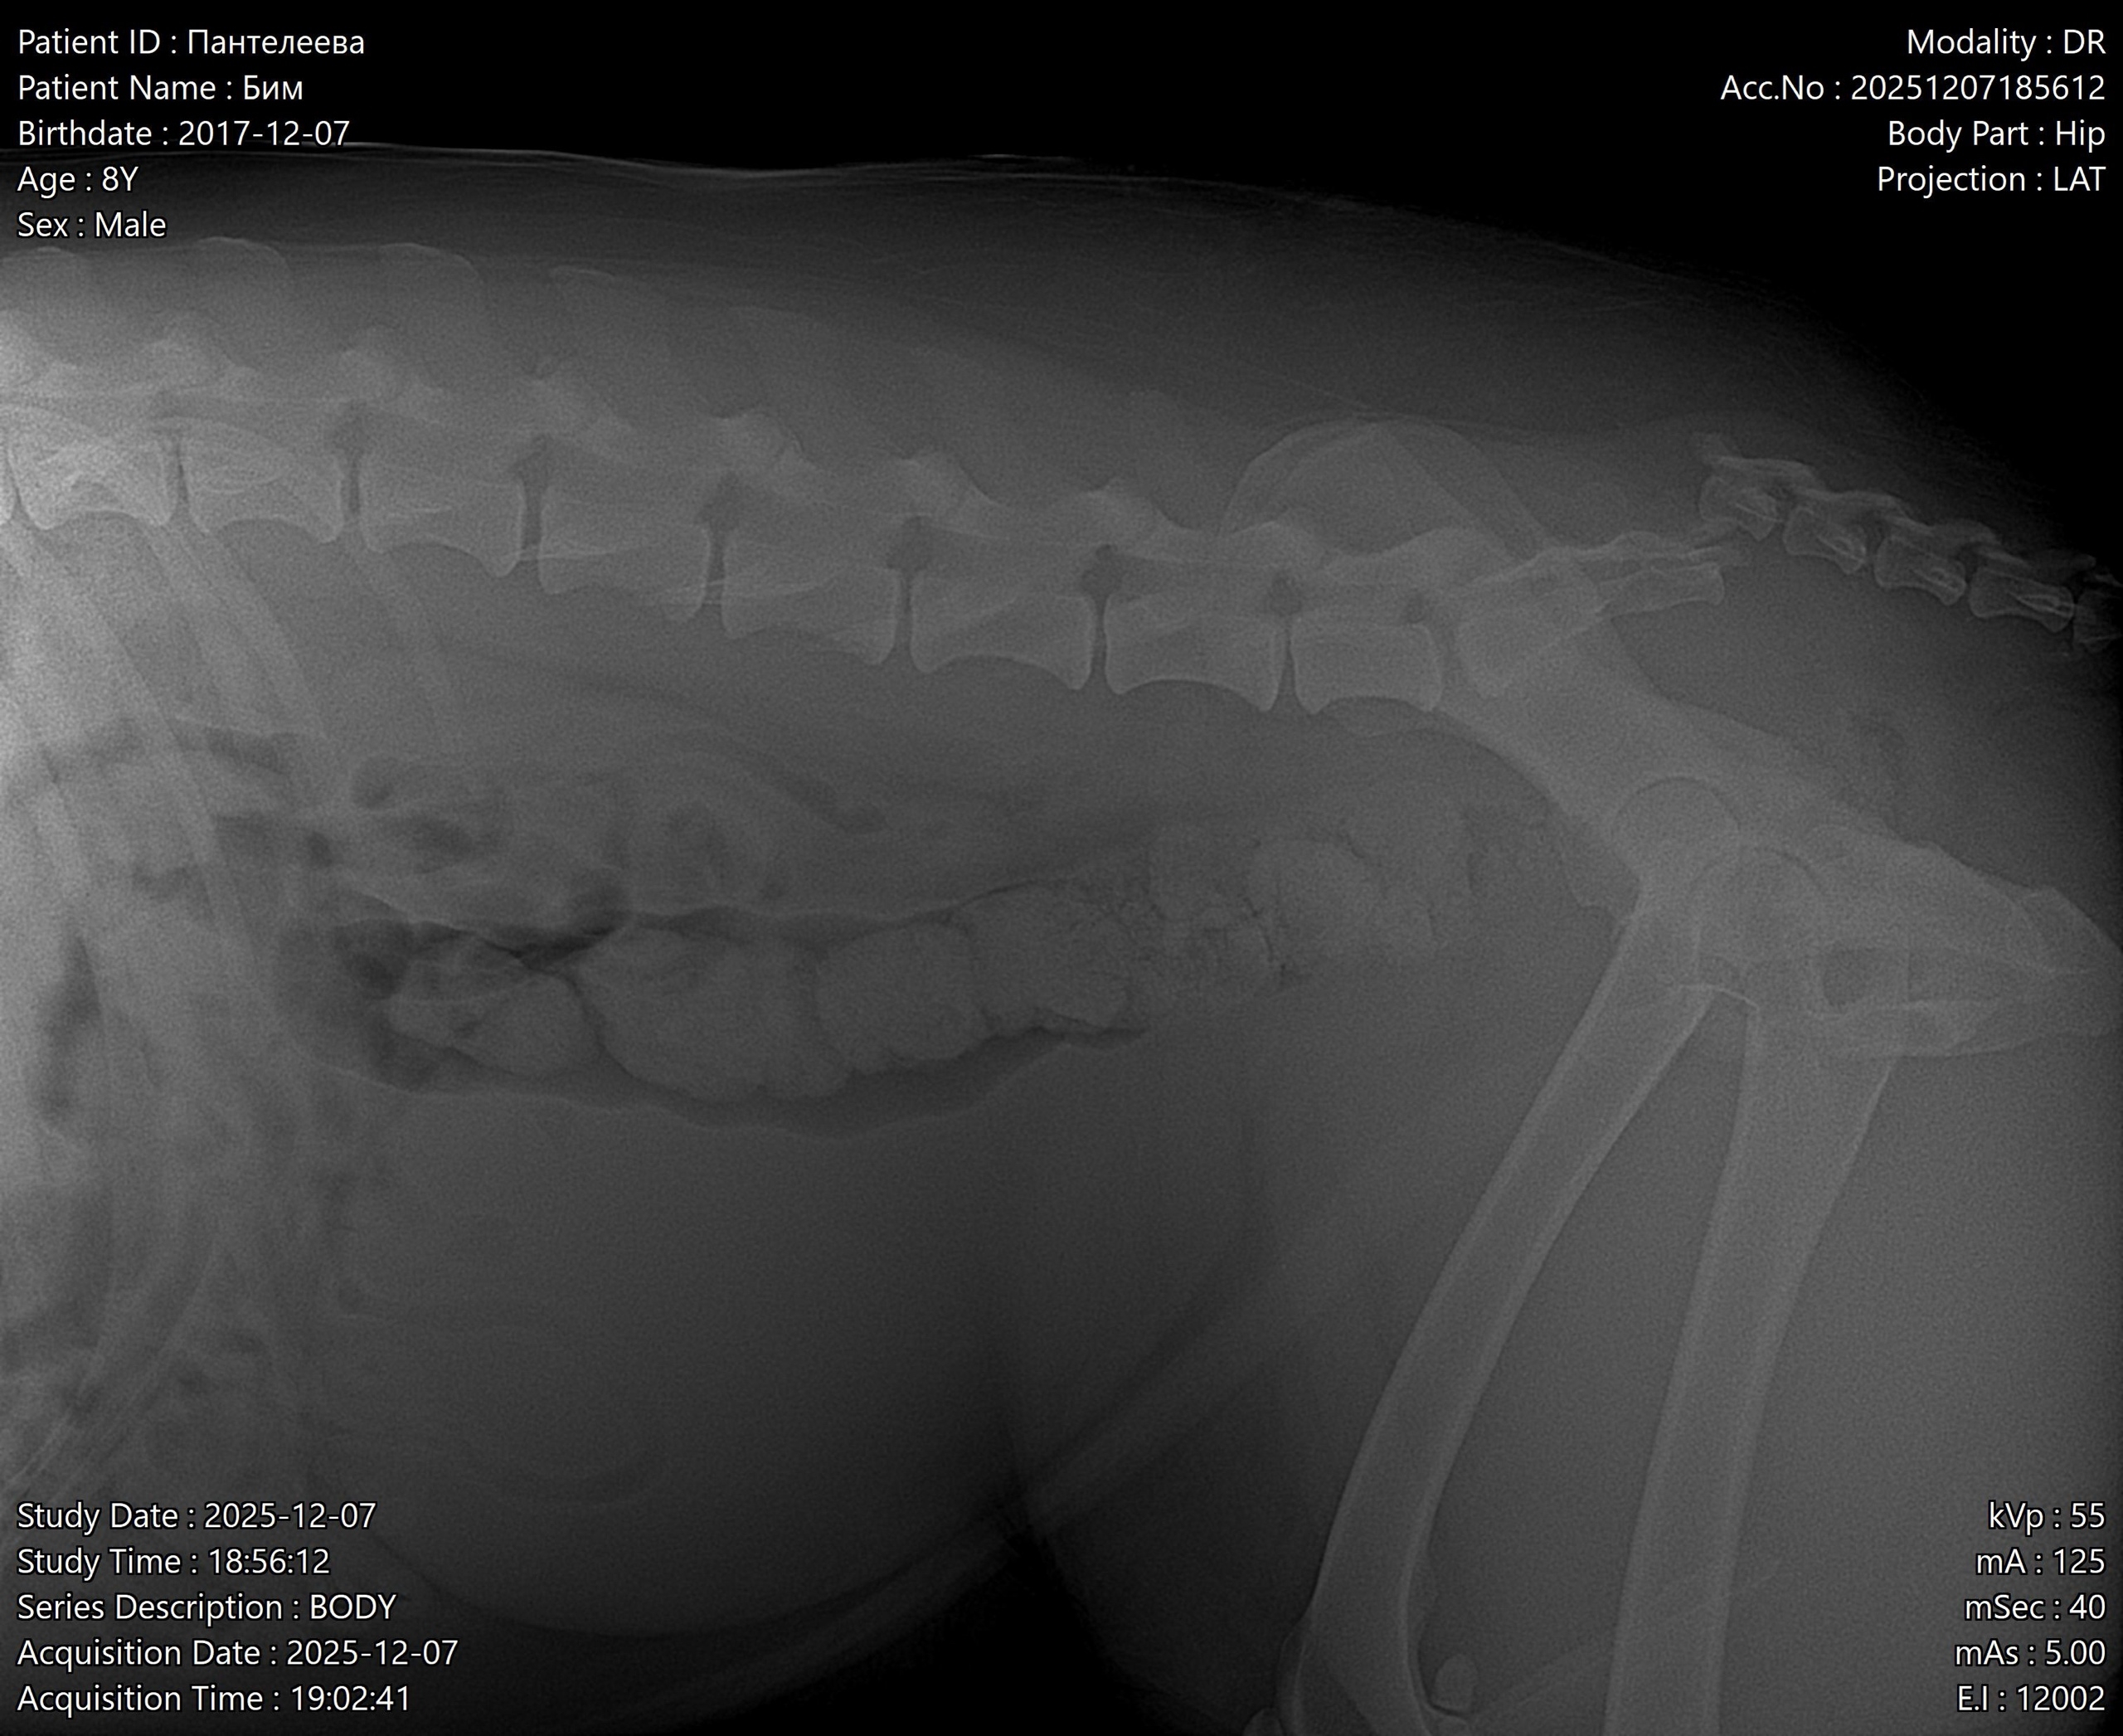

Недавно собачку (Бима ) Переехала «Газель »,ему очень сильно нужна помощь, видь его жизнь и так тяжелая у него нет дома и любящих хозяев.У собаки серьёзные травмы: (перелом таза ). Ветеринар сказал, что без операции он будет всю жизнь мучиться от боли в ноге и не факт, что вообще будет ходить😢